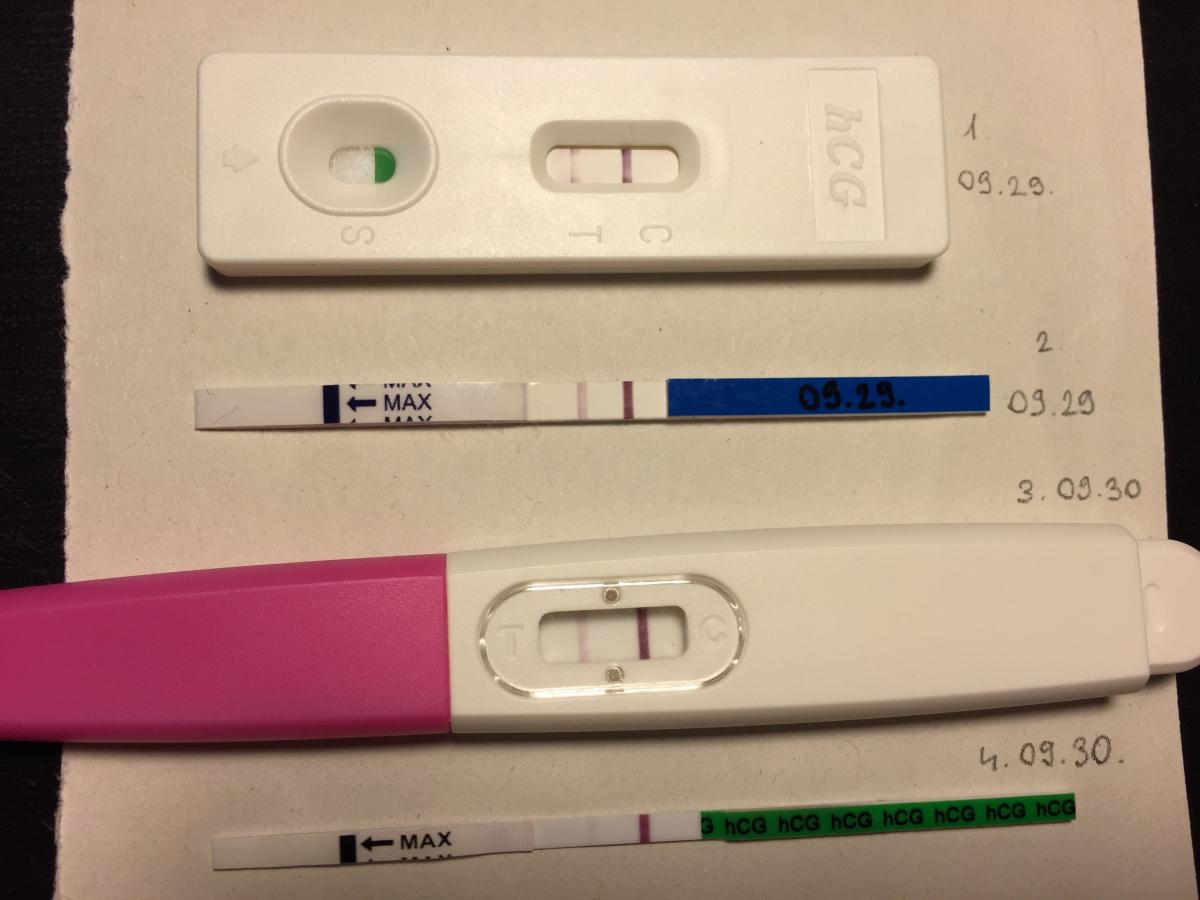

Bocsánat, hogy a ti csoportotokba írok, eddig az 1 éve próbálkozók táborába tartoztam... viszont tegnap életemben először csináltam egy (azaz kettő) terhességi tesztet és pozitív lett, de júniusi csoportot nem találtam és talán még korai is lenne.

szóval ma reggel is csáltam két tesztet, de az egyik szinte halványabb, mint a tegnapi, a másik meg alig látszik... volt valakivel ilyen? hogy nem erősödött feltűnően a T csík? vagy ez még nem baj? lehet annyira az elején vagyok, hogy még lassan nő a hCG?![]() (csatolok képet)

(csatolok képet)